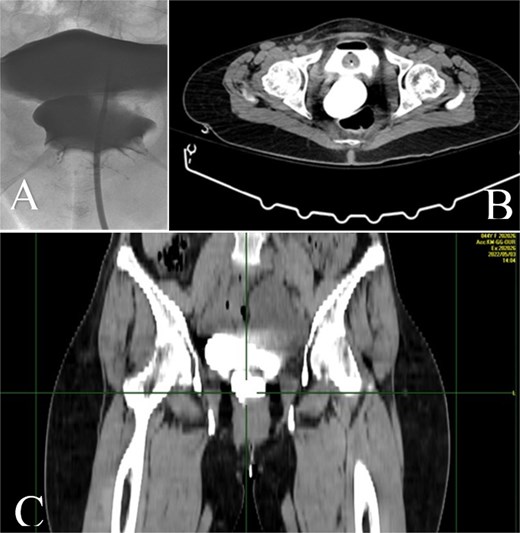

Two months later, the symptoms gradually reoccurred and a retrograde cystography and CT cystography were performed demonstrating the known UVF and as a new finding the formation of a VVF (Fig. 2). Based on these findings, a surgical repair with an open abdominal exploration was decided.

A: Retrograde cystography with contrast enhancement showing the existence of a VVF. B and C: CT cystography showing passage of contrast enhancement from the bladder to vagina, demonstrating the formation of a VVF.